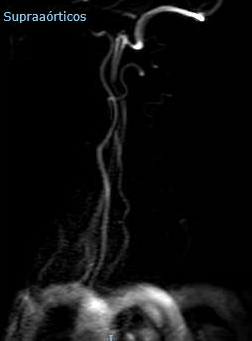

Ecografía Doppler de Troncos Supraórticos

Eje derecho: Velocidad sistólica (cm/s) Carótida Interna (CI) 300; Carótida Común (CC) 64. Relación CI/CC 4,7. Velocidad Diastólica Final (VDF) en la CI 79. Estenosis superior al 70%. Placa heterogénea, irregular, hiperecoica y calcificada. Subclavia normal. Distancia bifurcación normal. Se visualiza CI distal sin alteraciones.

Eje izquierdo: Velocidad sistólica (cm/s) CI 120; CC 92. Relación CI/CC 1,3. VDF CI 30. Estenosis inferior al 50%.

Conclusiones: Eje derecho con abundante ateromatosis de contenido mixto en carótida común y bulbo carotídeo. Estenosis de carótida derecha superior al 70% y estenosis de carótida izquierda inferior al 50%.